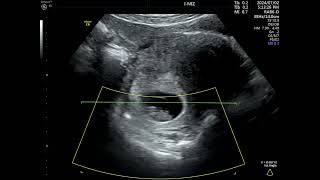

8 Weeks Pregnant: First Movements via 4D Ultrasound Scan